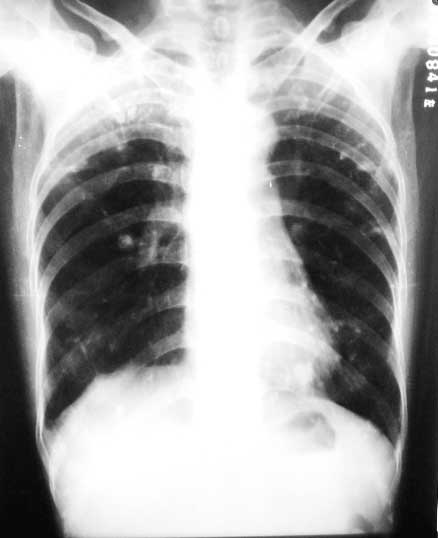

标题: X0226:[原创]两肺结节状高密度

f/63y,胸痛数天,曾患结核性胸膜炎。

1、双上中继发性肺结核,右侧胸膜粘连;

双上肺结节条索。点仗钙化。透光度增强,诊断肺结核,肺气肿

双上肺陈旧性结核,右侧胸膜粘连,肺气肿右侧肺门可能是伪影

两肺钙化灶,两上胸膜增厚、粘连

意见:1陈旧性肺结核;2右侧胸膜粘连;3两中下肺气肿。